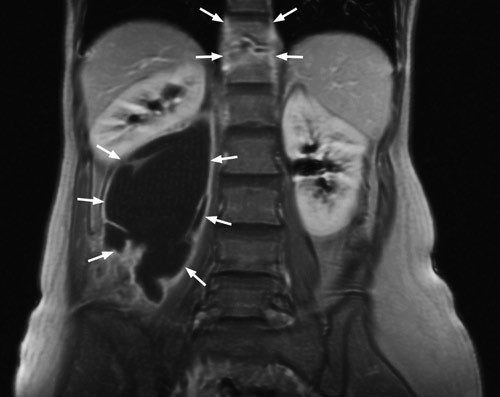

She had an erythrocyte sedimentation rate of 49 mm/h. Other general blood tests, including an HIV test, were normal. Both chest X-ray and urine culture for mycobacteria were negative. MR abdomen revealed findings as for spondylodiscitis at level Th11/Th12 with a large depression abscess in the right m.psoas (left). The abscess measured approximately 14 cm craniocaudally and extended caudally to the level of the L5 corpus vertebrae. A section through the abscess is seen on the right. Microscopy of the abscess material revealed no findings of acid-resistant rods. Culturing and polymerase chain reaction revealed findings of Mycobacterium tuberculosis. About 350 ml pus was drained off and long-term tuberculostatic treatment was started. The woman is being monitored regularly through outpatient follow-up.